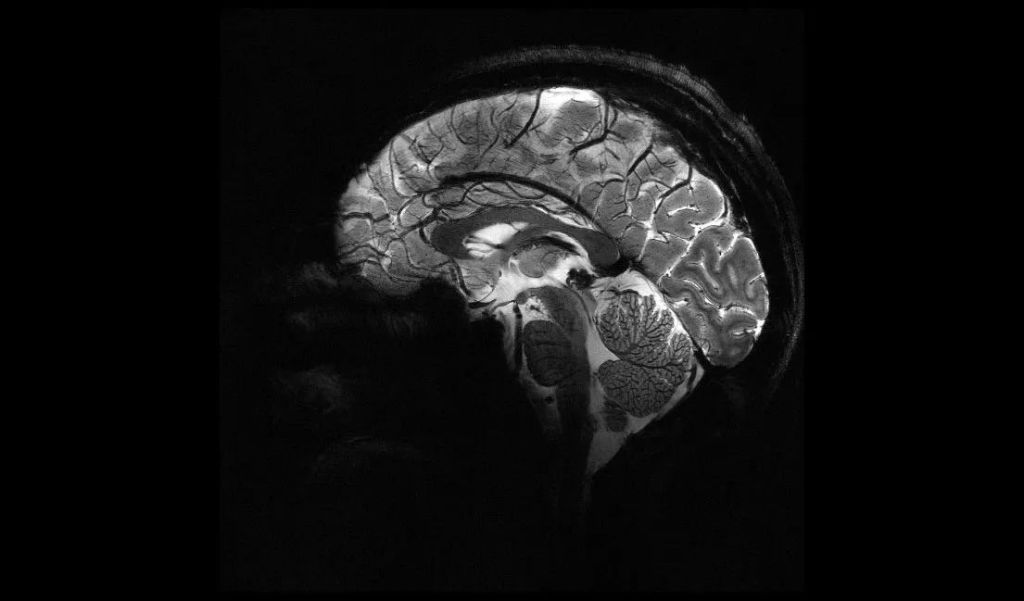

Le cerveau dĂ©voilĂ© comme jamais grâce Ă l’IRM le plus puissant au monde

Le CEA a dĂ©voilĂ© des images du cerveau obtenues avec le scanner IRM Iseult, dotĂ© d'un champ magnĂ©tique de 11,7 teslas, le plus puissant au monde. Ces images offrent une rĂ©solution inĂ©galĂ©e et permettent de dĂ©couvrir de nouveaux dĂ©tails sur l'anatomie, les connexions et l'activitĂ© du cerveau humain. Les applications mĂ©dicales de cette avancĂ©e sont nombreuses, notamment dans le diagnostic…